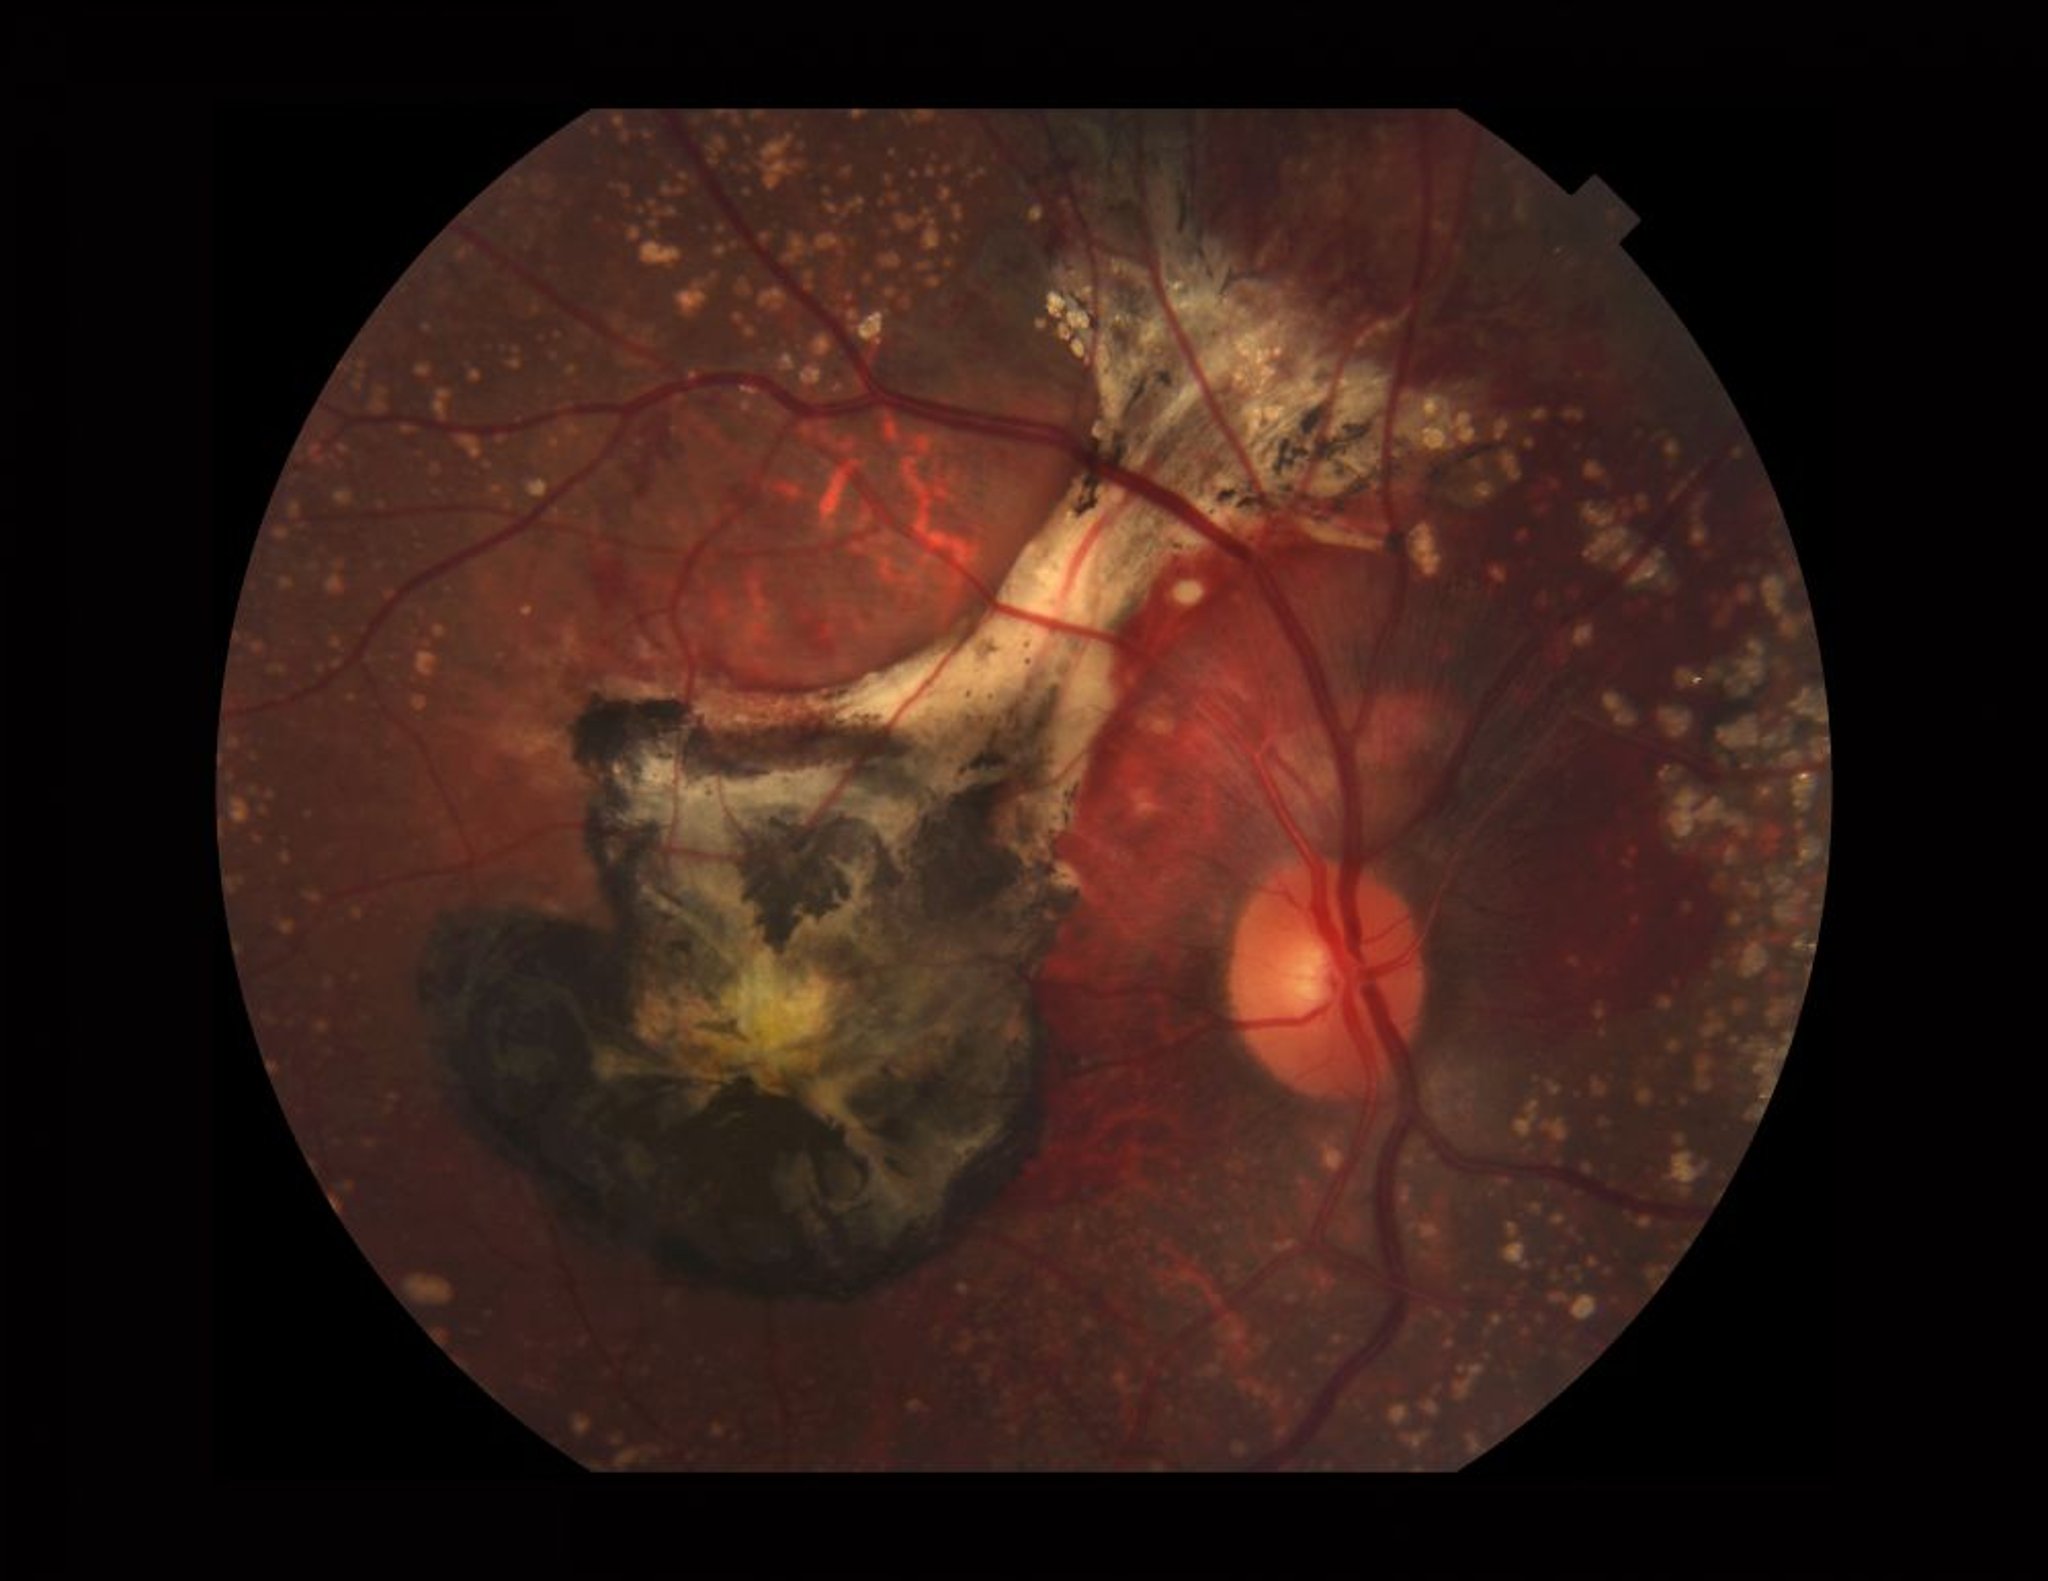

滲出型加齢黄斑変性を発症した網膜の写真。この画像には,石灰化したドルーゼン,網膜下出血,脈絡膜新生血管膜(古い血液および線維化による黒い部分),および黄斑部のキサントフィル色素が認められる。